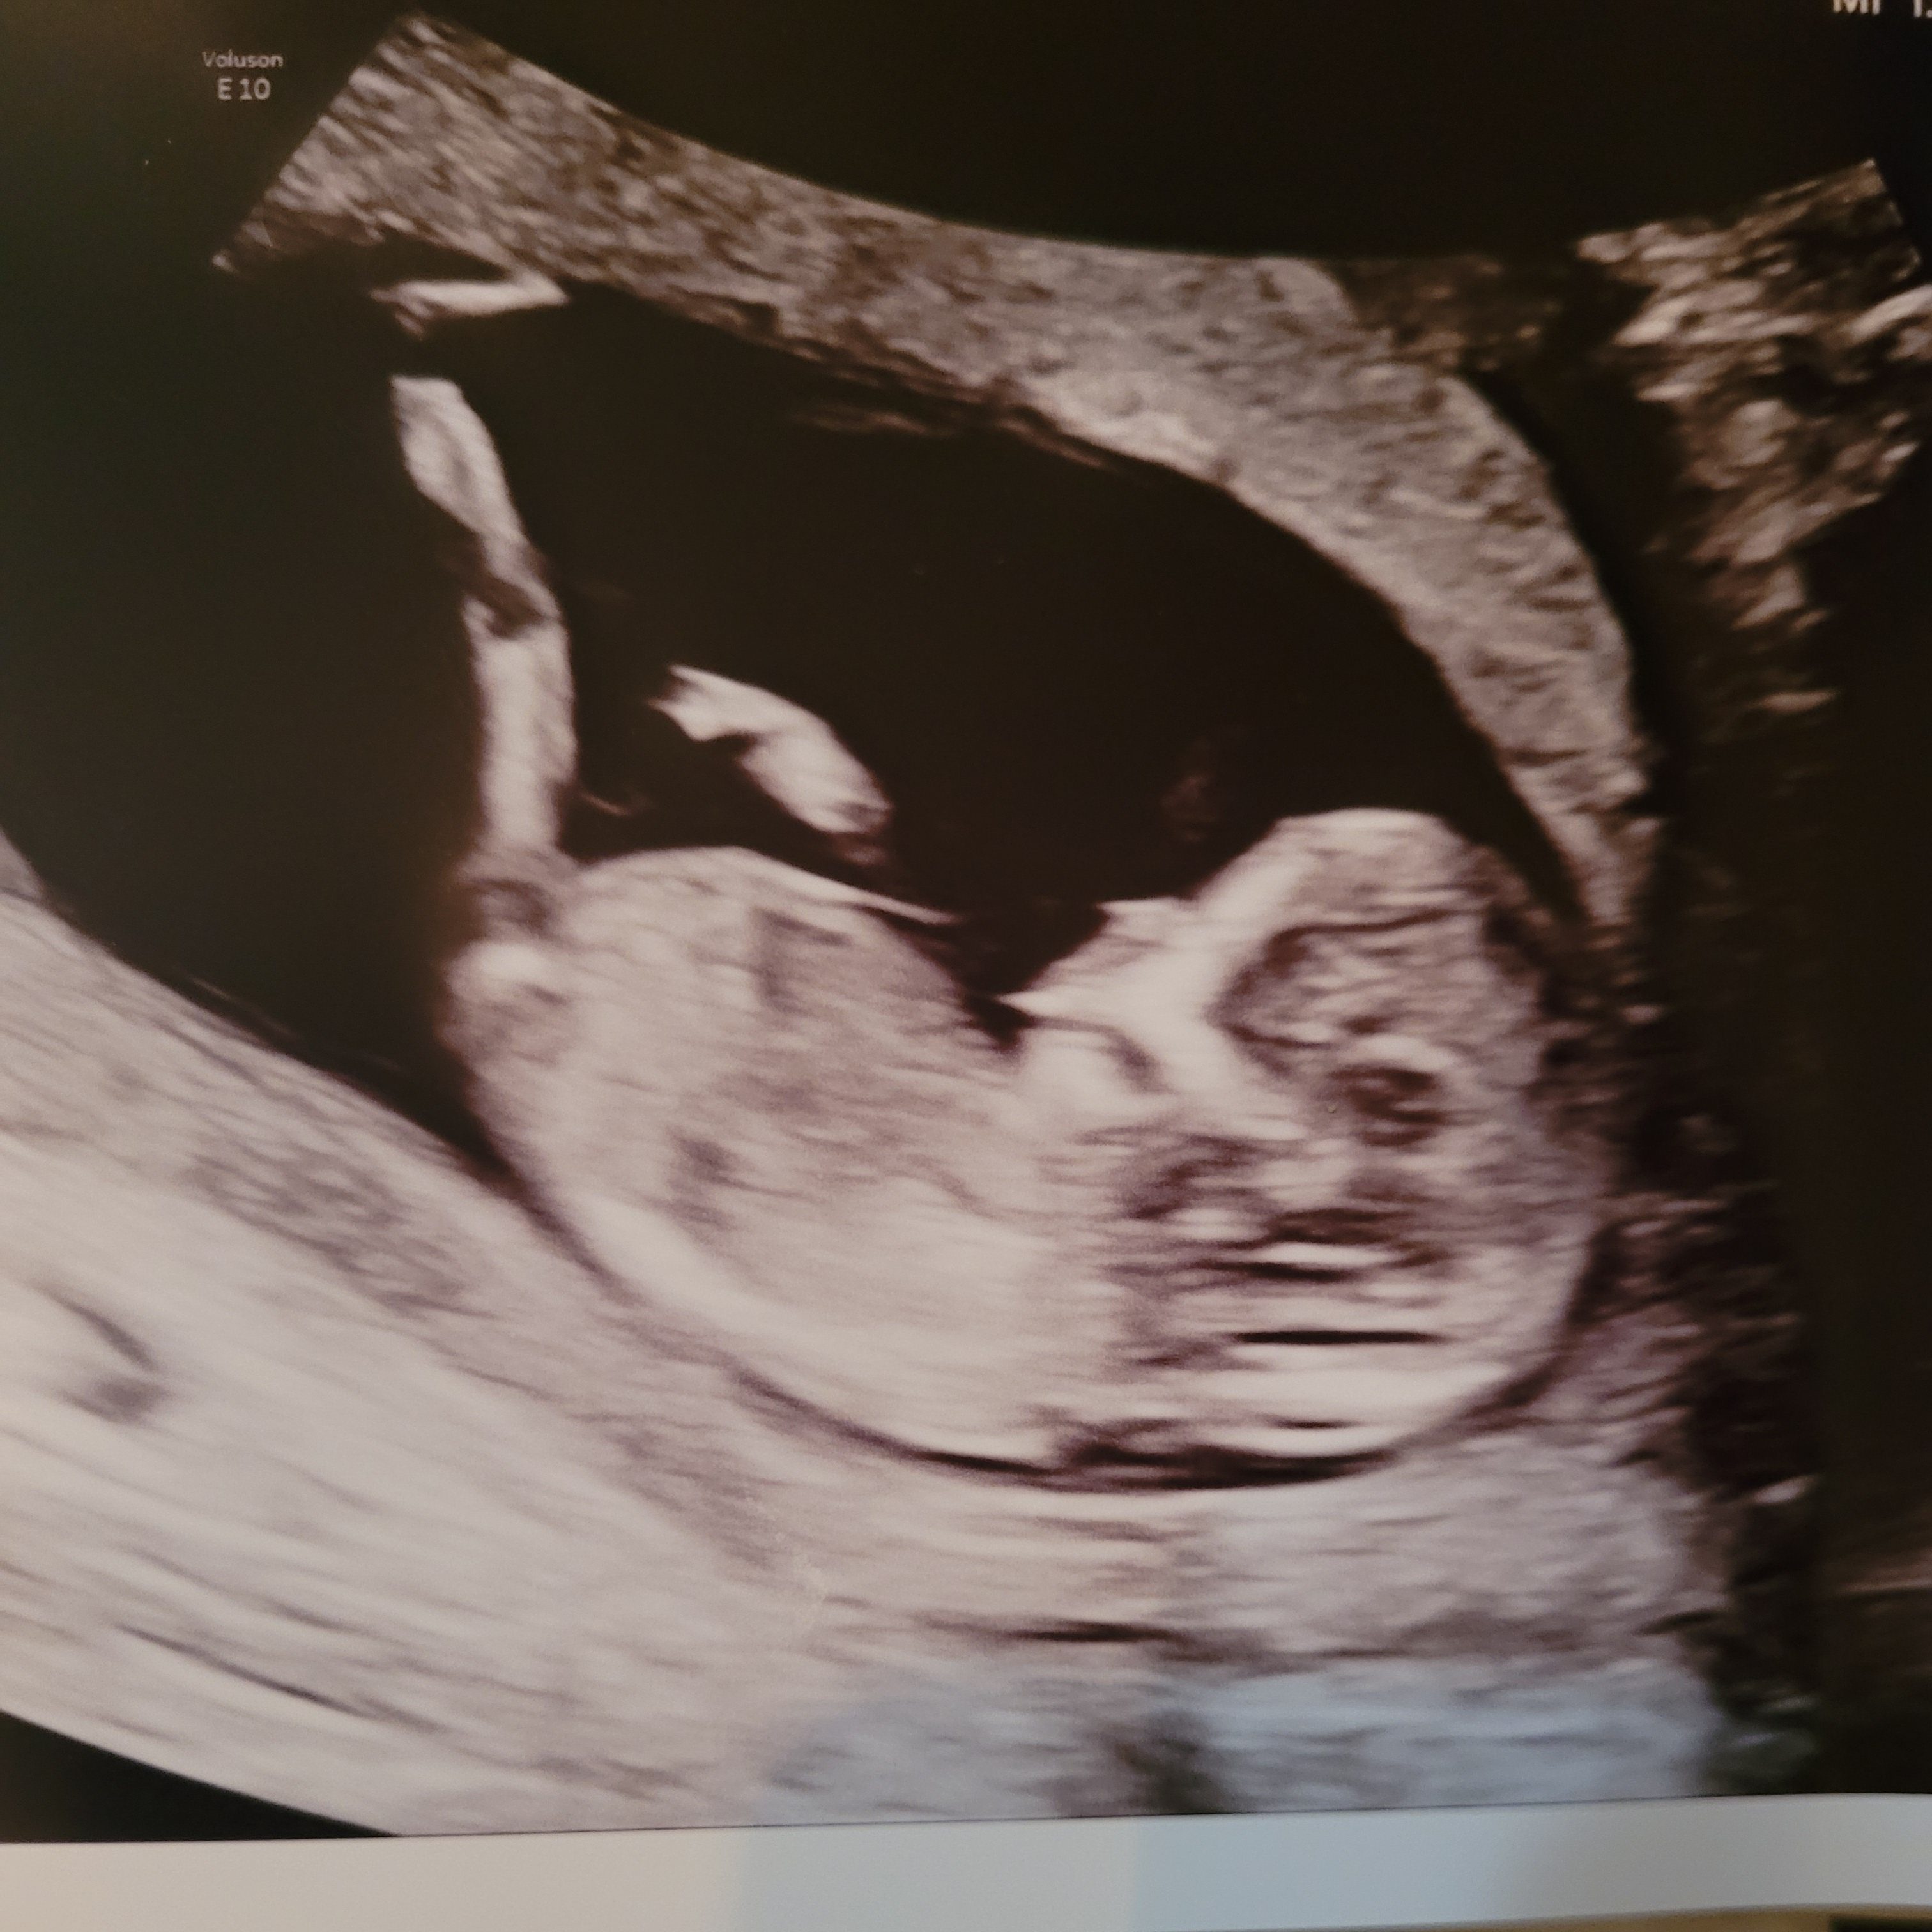

- And best for last: a followup to last month’s exciting news. The baby is doing great, but the nausea is real. We thought the it was getting better, but one day off nausea meds proved otherwise. On a positive note, we got more ultrasound pictures, and our little jellybean looks quite energetic. They caught our baby kicking and stretching, and the experience is exhilarating. But no, we still do not know the gender.